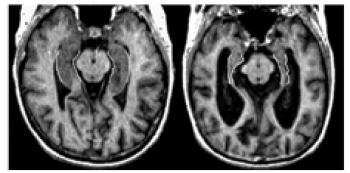

When brain cells degenerate and die, the brain dramatically shrinks in some areas of the brain.

This was first observed when Dr. Alzheimer studied the brain of Auguste Deter, the first person to be officially diagnosed with Alzheimer's disease, and it's still observed in people with Alzheimer's disease today.

To illustrate, the image here shows that a person who doesn't have Alzheimer's disease (left) has more brain tissue than a person who has Alzheimer's (right).

This shrinkage continues as the disease progresses, affecting the function of the brain and increasing the severity of symptoms.